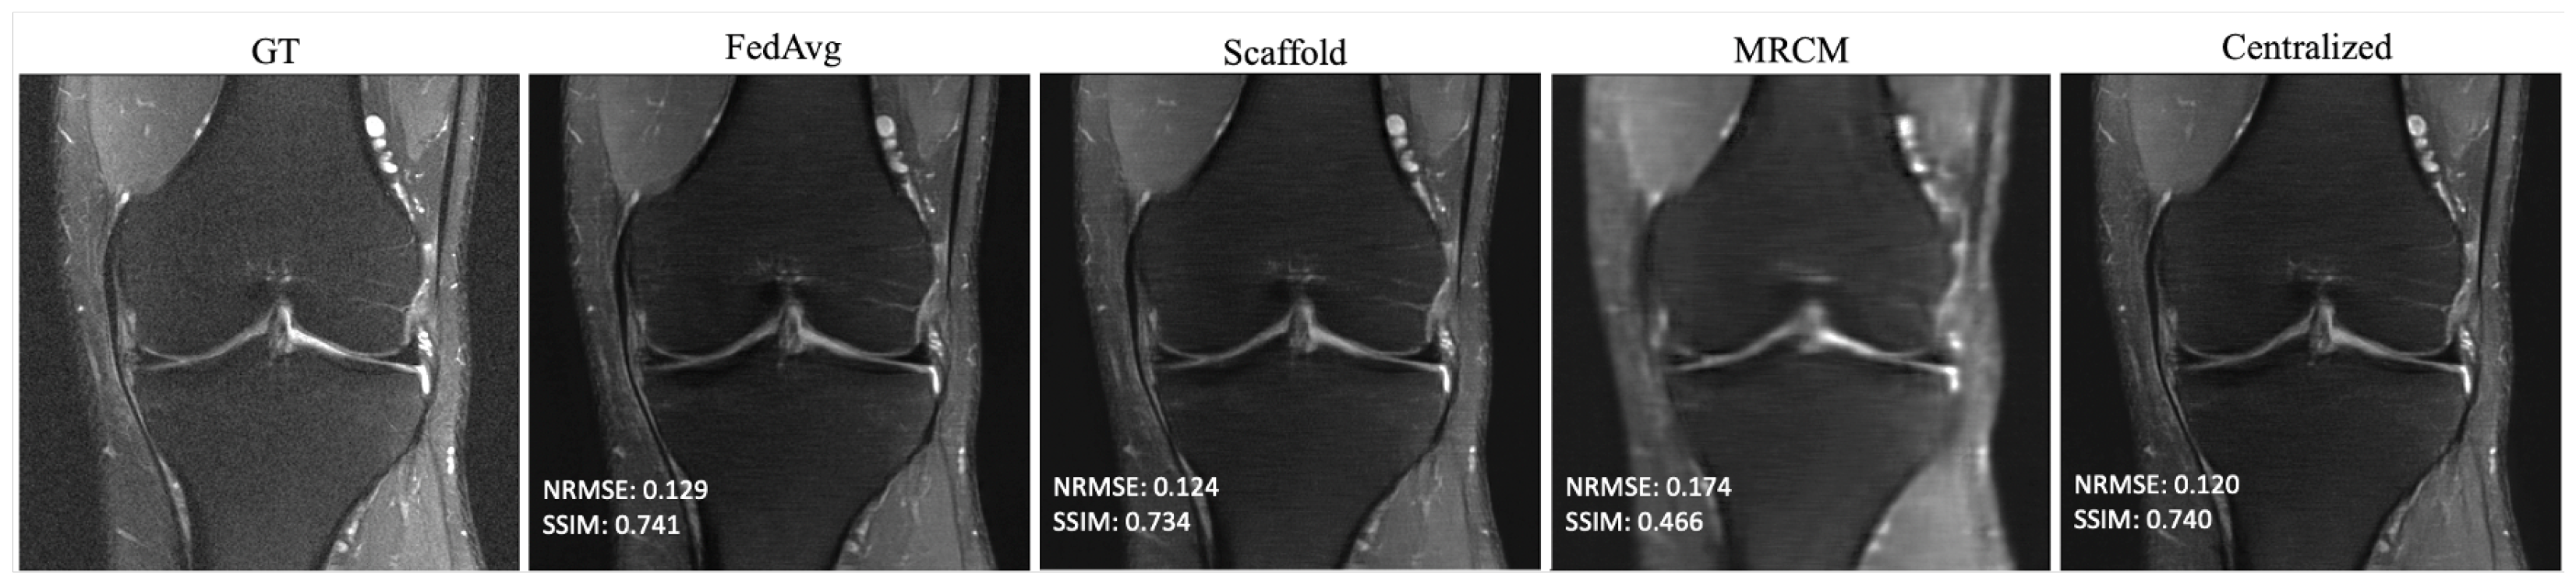

The results of non-i.i.d. experiments are summarized in Table 3 and Table A1 in Appendix A for all fastMRI sites that participated in training. In this case, centralized and FedAvg perform about the same, while the adaptive federated algorithms typically perform slightly better. FL-MRCM is not competitive in this regime. Figure 4 shows example reconstructions of slices from two different sites. In this case, there is a clear qualitative and quantitative improvement between Scaffold and FedAvg, where the latter performs on par with centralized training.

Figure 4. Example reconstructions obtained in the non-i.i.d. client scenario with 240 communication rounds: (Top) Brain T1-POSTCON 3T, (Bottom) Knee PD 3T.

Bioengineering 10 00364 g004